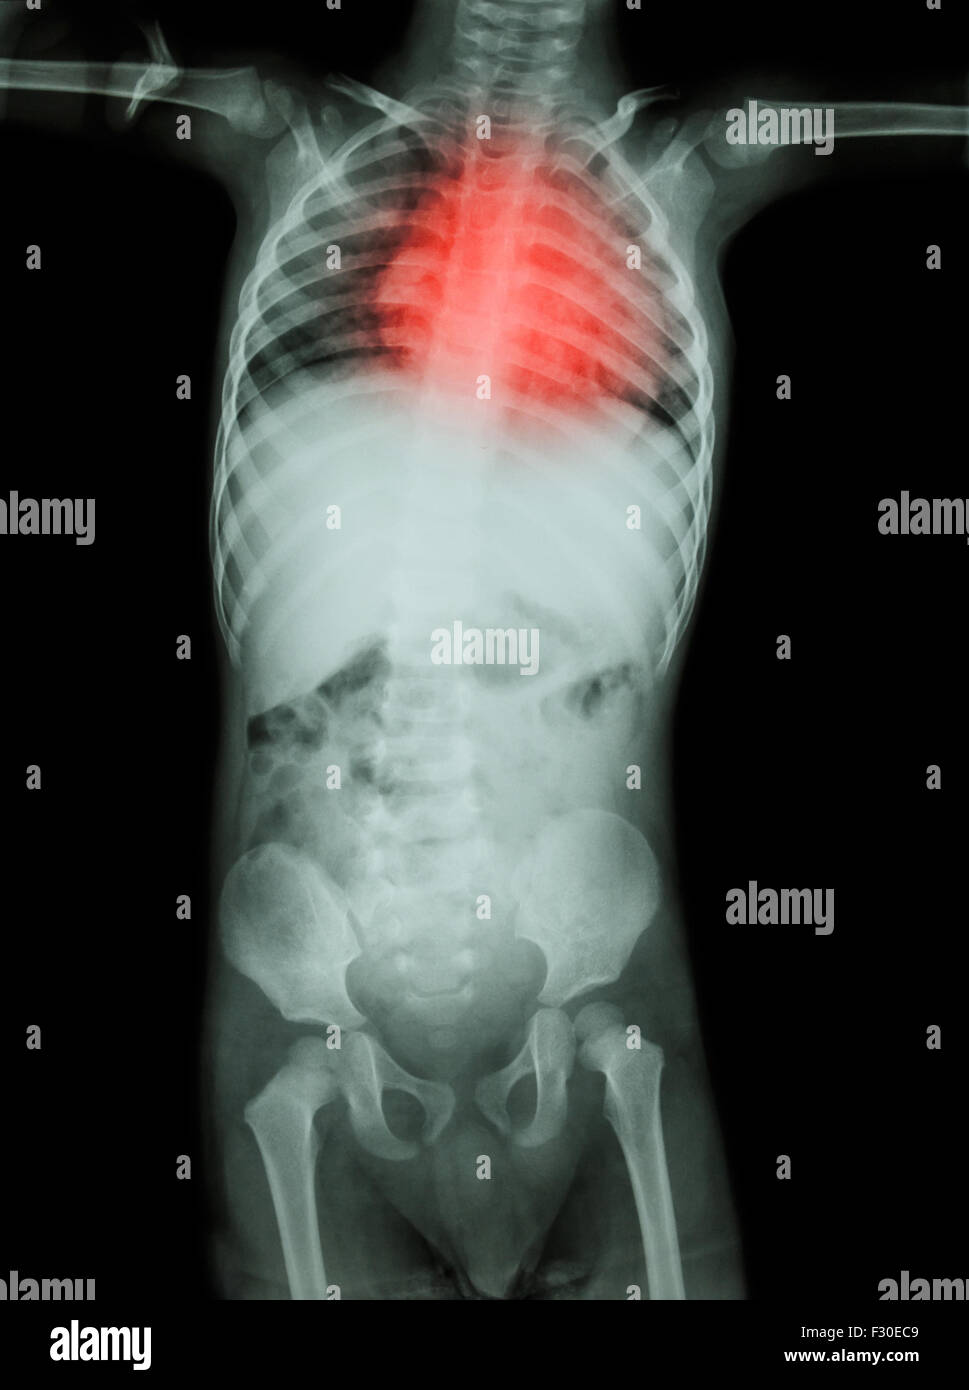

Congenital Heart Disease , Rheumatic Heart Disease ( Xray Whole Body Chest X Ray Findings In Rheumatic Heart Disease Symptoms of rheumatic heart disease depend on the degree of valve damage and may include: This topic will review the clinical manifestations and diagnosis of rhd. Magnetic resonance imaging (mri) and ultrasound are most commonly used in. Shortness of breath (very often with activity or. The management of rhd and the pathogenesis,. On echo there was severe mitral regurgitation, moderate. Chest X Ray Findings In Rheumatic Heart Disease.

Congenital Heart Disease , Rheumatic Heart Disease ( Xray body of Chest X Ray Findings In Rheumatic Heart Disease Magnetic resonance imaging (mri) and ultrasound are most commonly used in. On echo there was severe mitral regurgitation, moderate mitral stenosis,. Shortness of breath (very often with activity or. Physical exam was significant for right lung crackles on inspiration and grade 3 holosystolic murmur with normal respiratory rate and. The management of rhd and the pathogenesis,. This topic will review. Chest X Ray Findings In Rheumatic Heart Disease.

Rheumatic heart disease , Valvular heart disease ( Film xray body of Chest X Ray Findings In Rheumatic Heart Disease On echo there was severe mitral regurgitation, moderate mitral stenosis,. Symptoms of rheumatic heart disease depend on the degree of valve damage and may include: The management of rhd and the pathogenesis,. Rheumatic heart disease is a chronic condition caused by rheumatic fever, leading to permanent damage to heart valves and requiring ongoing medical management. Magnetic resonance imaging (mri) and. Chest X Ray Findings In Rheumatic Heart Disease.